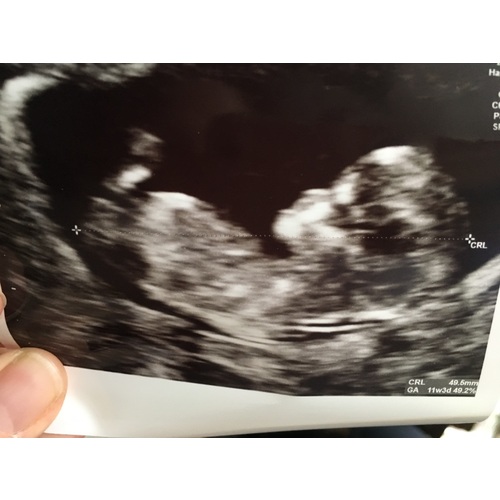

Oh, ik ben pas 11 weken en 4 dagen.. ik ben er nog niet zo mee bezig eerlijk gezegd.. ik heb 6 januari een echo (dan ben ik 15 weken) ik hoop dat ze dan al t geslacht kunnen zien. Ik ben zwanger van me 1e dus het is sowieso allemaal hartstikke nieuw voor me. Maar vind het super leuk om mee te lezen hier! Zo leer ik ook steeds nieuwe dingen